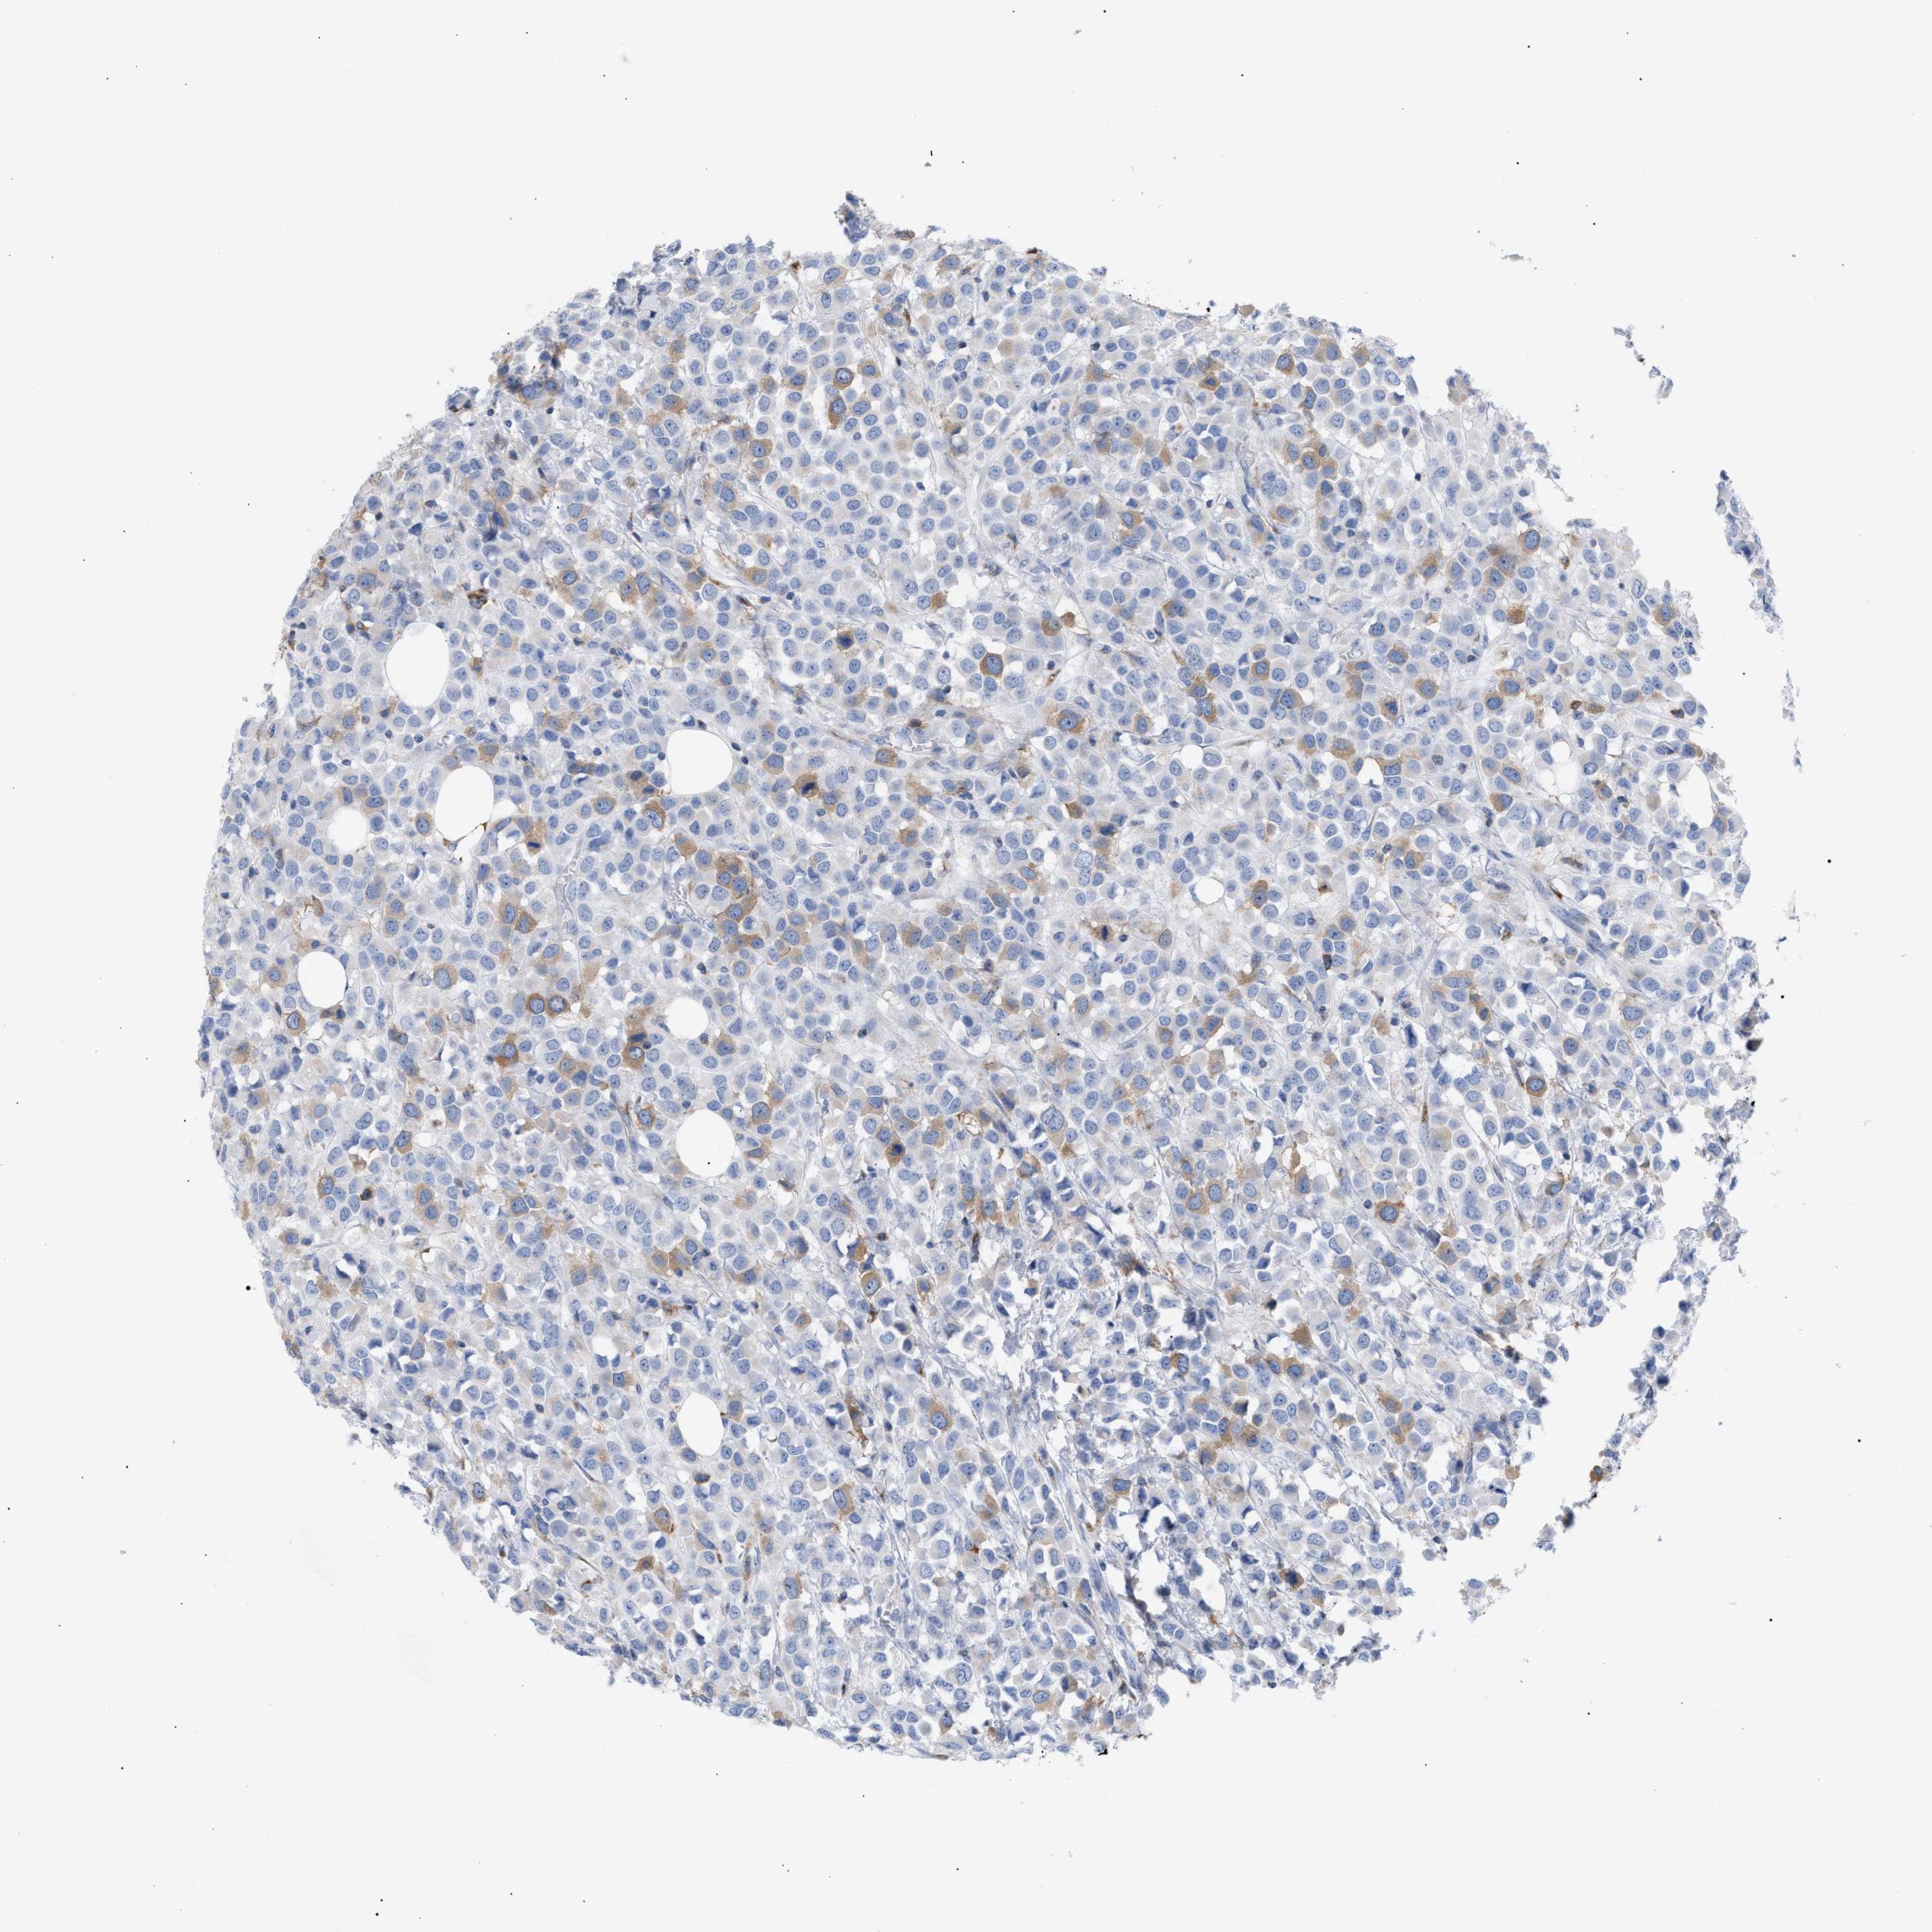

CANCER BREAST CANCER Show tissue menu

BRCA TCGA BRCA VALIDATION PROTEIN EXPRESSION